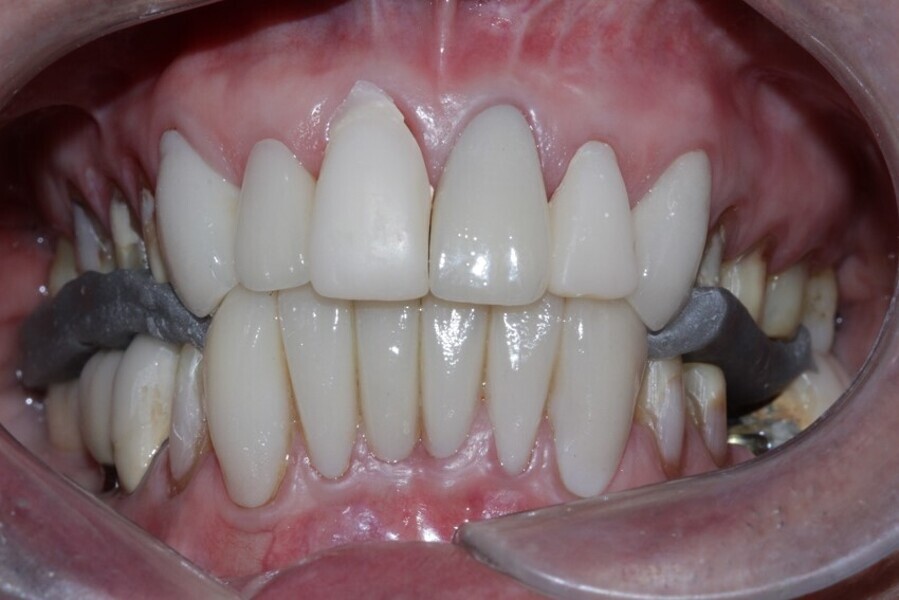

Figure 26 Closed mouth post op